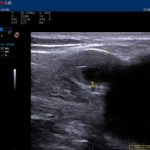

ehit-2class-om